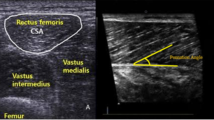

The US image was taken 15 cm from the upper edge of the patella, where transverse images were obtained with a B-mode ultrasound device (The Esaote MyLab One; Esaote, Genova, Italy) equipped with a linear array transducer 5 cm long. The transducer was placed perpendicular to the axis of the limb and transversely to the direction of the fibres. Older adults were seated in a chair with their hip and knee at 90° of flexion (Supplementary Appendix B). The evaluator was placed in front of the patient, holding the transducer with one hand and the participant's leg with the other one. Before performing the US measurements, the older adults rested for 5 min to avoid bias in measuring muscle thickness and echo-intensity. To adequately capture a static image in a contraction state, the participant performed a manually resisted voluntary isometric contraction of 5 s by the physician. The parameters used to acquire US images included the B-mode, a frequency of 10 MHz, 4 cm deep, and 42% of the gain. Coupling gel was abundantly applied to minimise distortion generated by underlying tissues. Shaving was not needed.

Ultrasound imagesof the four types classified based exploratory hierarchical cluster: (A) normal MT, FT, MEI and FEI; (B) increased FT, relatively decreased MT to FT, slightly high FEI and slightly low MEI; (C) very increased FT, normal MT, decreased MEI and slightly high FEI; (D) decreased FT and MT and very high MEI with normal FEI. Non-con MT: Non-concentration muscle thickness; Non-Con FT: Non-concentration subcutaneous fat tissue thickness; Non-con MEI: Non-concentration muscle echo-intensity; Non-Con FEI: Non-concentration subcutaneous fat tissue echo-intensity; Con MT: concentration muscle thickness; ConFT: concentration subcutaneous fat tissue thickness; Con-MEI: concentration muscle echo-intensity; Con-FEI: concentration subcutaneous fat tissue echo-intensity. A,B,C,Dp < 0.05; A*, B*, C*, D*p < 0.001.